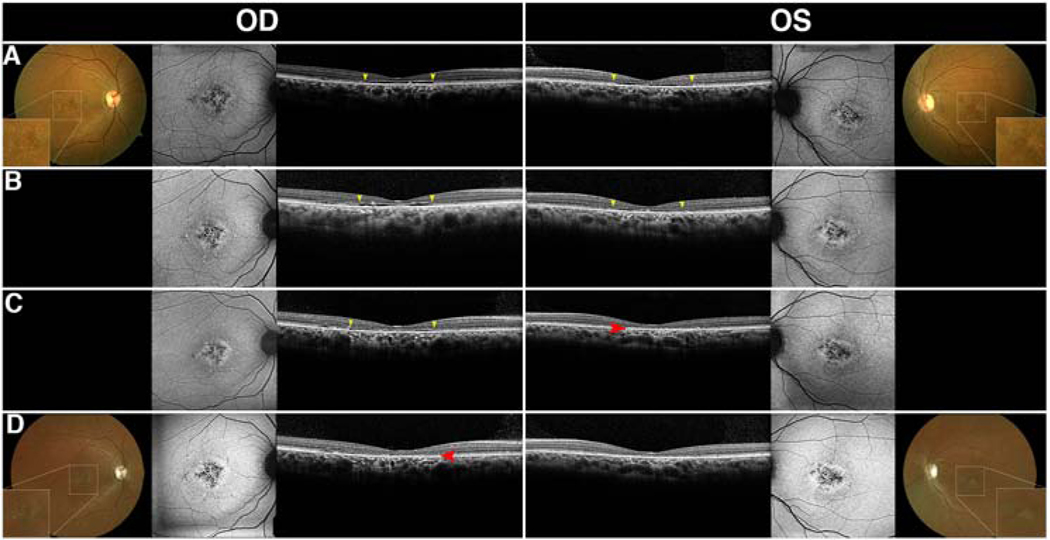

On SD-OCT, seven (P3, P4, P9, P30, P32, P35, and P36) out of 19 patients with Stargardt disease or cone-rod and macular dystrophies presented with interocular discordance of the optical gaps or showed progression from one stage to another at different time points throughout their follow-up (Fig. 4). Typically, this was seen as the collapse of the optical gap in one eye while the optical gap in the other eye retained the integrity of the cavity. Using the staging system previously described for Stargardt disease, this meant that one eye progressed from Stage II to Stage III while the other remained in Stage II.3 The residual patterns of the optical gap phenotype can sometimes be seen in these patients following atrophy. This is characterized by an optically empty space between the preserved EZ-line and the location of neurosensory collapse (Fig. 4, white arrows), which is eventually eliminated by progressive atrophy.3 In contrast, all achromatopsia patients with the optical gap phenotype and confirmed CNGA3, CNGB3, PDE6C, or ATF6 mutations were found to have interocular agreement of the phenotype based on cross-sectional analysis of 7 patients and longitudinal analysis of 5 patients.

Figure 4. Interocular discordance in patients with optical gaps.

Interocular discordance of optical gap was observed in five patients (P3, P4, P9, P30, P32) with cone-first retinal degenerations at presentation (A-E). Three patients (P3, P4, P9) were found to have asymmetric disease with optical gap and residual foveal photoreceptors in one eye and collapse of the retina into the cavity with loss of the inner and outer retinal layers in the other eye (A-C). P30 presented a preserved optical gap in the right eye while the left eye demonstrated detachment of the retinal pigment epithelium and consequent occupation of the space. P32 presented with a visible optical gap in the left eye and intermittent disruptions of the ellipsoid zone-line indicative of impending gap formation in the right eye.